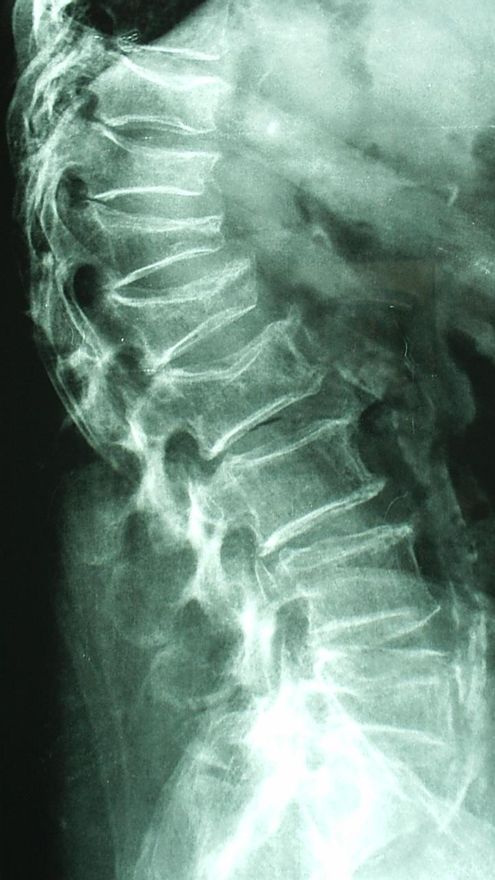

Estas fracturas se clasifican en vertebrales, no vertebrales y fractura de fémur. La fractura vertebral es a menudo asintomática y solo puede diagnosticarse tras la realización de una radiografía de columna lateral. La fractura de radio distal (o fractura de Colles) suele producirse al caer el paciente al suelo y apoyar la mano. La fractura de la extremidad proximal del fémur, conocida como fractura de cadera, es la más grave. Suele producirse en personas de edad avanzada con una edad media de 80 años y prácticamente todas deben ingresar en un hospital y ser operadas. Un porcentaje pequeño pero no desdeñable de estos pacientes fallecen en la fase aguda del ingreso hospitalario. Asimismo, es dramática la evolución posterior a la fractura, pues aproximadamente la mitad de estos pacientes no vuelven a sus domicilios y terminan ingresados en centros de larga estancia o de crónicos. Existen estudios que sugieren que los varones con fractura de cadera tienen una peor evolución y una mayor mortalidad que en el caso de la mujer.

La única manera de diagnosticar la osteoporosis es realizando un tipo especial de radiografía, que es la denominada densitometría ósea. Con ella, se estima la densidad mineral ósea, tanto en la columna lumbar como en la extremidad proximal del fémur. Los valores obtenidos se comparan con los ya establecidos como normales en la población española y a partir de unos criterios acordados por la Organización Mundial de la Salud (OMS) se diagnostica la osteoporosis. Existen otras técnicas para estimar el riesgo de fractura como los ultrasonidos en el calcáneo, que tiene sus ventajas (no irradia, ya que son ultrasonidos) como inconvenientes (no sirven para diagnosticar la osteoporosis, solo el riesgo de fractura).